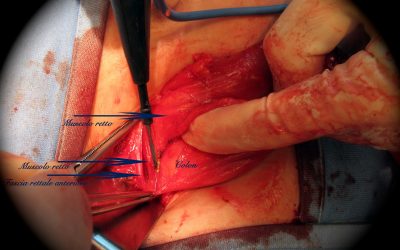

Ernioplastica inguinale con protesi interfasciale: note di tecnica chirurgica

di Enrico Ganz Introduzione Attualmente una delle più comuni tecniche di ernioplastica per la correzione dell’ernia inguinale monolaterale non recidiva, sia non complicata, sia complicata da strangolamento (27), prevede l’utilizzo di una rete protesica...